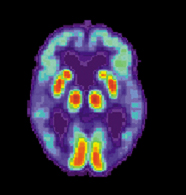

PET imaging has been widely used by neuroscientists to better understand what areas of the brain are activated for a variety of mental tasks and for diagnosis of brain diseases. An example of the latter is shown below in Figure 18. Two brain scans demonstrate drastically different levels of metabolic activity between a normal brain and that of an Alzheimer’s patient.

(a)PET scans of a normal brain.

(b)PET scans of an Alzheimer’s Disease brain.

Figure 18:Image from http://